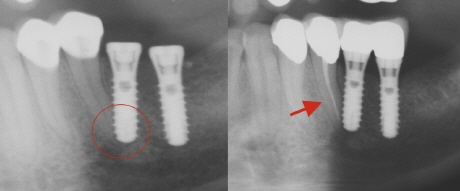

Die Schädigung von Nachbarwurzeln ist immer eine Folge fehlender Planung. Weder die Position der Implantate zueinander, noch die Implantatachse sind in diesem Fall richtig bestimmt worden. Auf dem Bild oben links sieht man, wie der Zahn durch das Implantat verletzt wurden (roter Kreis). Dies hatte zur Folge, dass der "angebohrte" Zahn mit "seinem Leben zahlen" musste und eine Wurzelfüllung benötigte (roter Pfeil).

Das Röntgenbild oben zeigt zwei viel zu dicht beieinander liegende Implantate (gelber Kreis) und ein von der Implantatachse ungünstiges Implantat, welches eine natürliche Zahnwurzel verletzt.